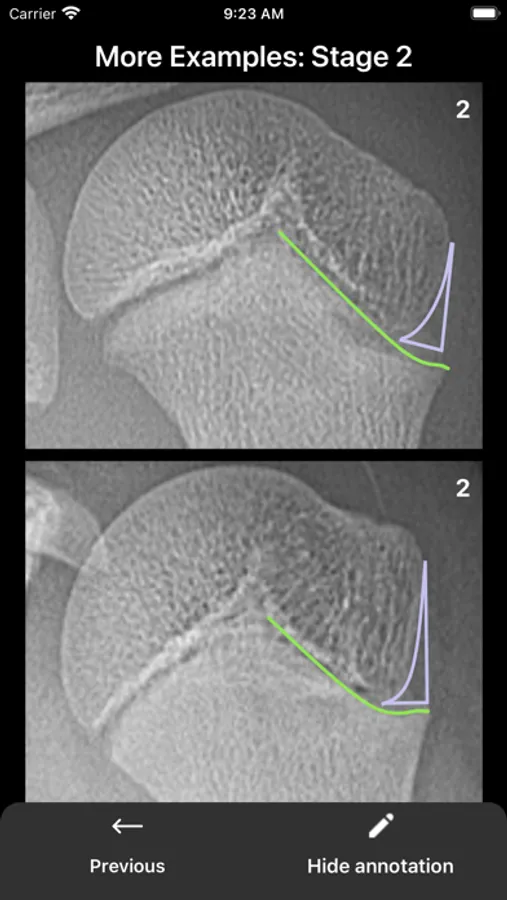

Optimized Oxford Hip Skeletal Maturity System (Hip)